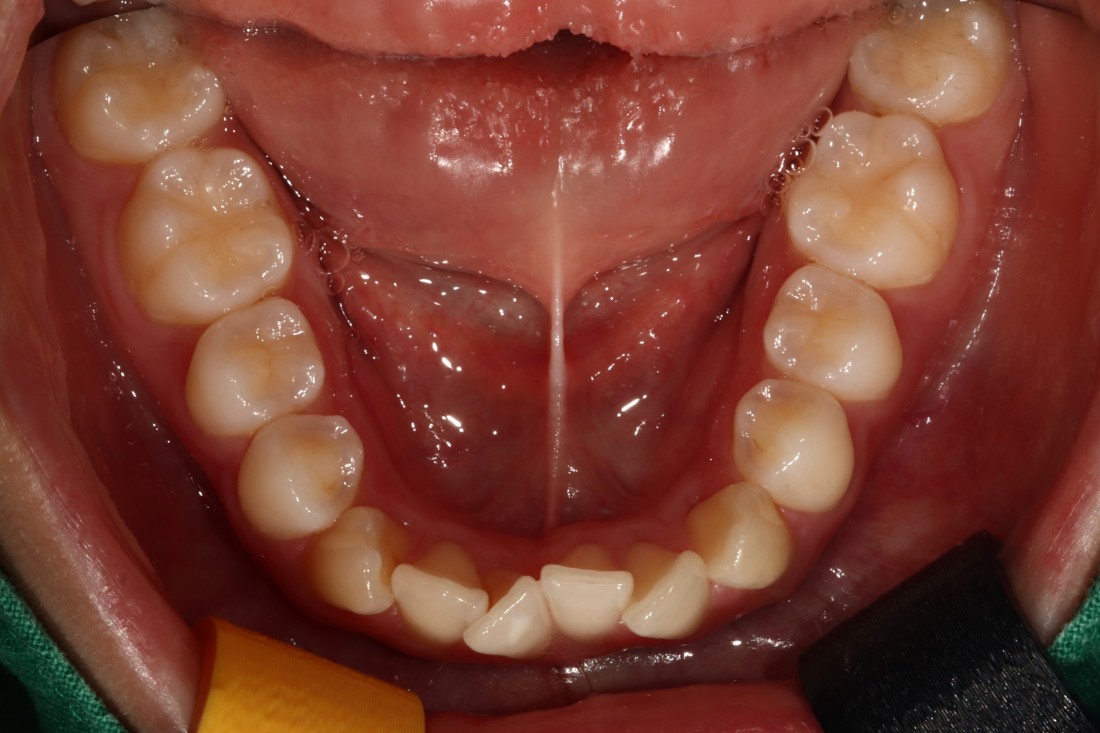

특히 교정진료를 받을 때는

치아를 발치해야 하는 경우도 있고,

충치치료를 동시에 진행해야 하는

케이스도 많은데요.

광주 교정치과 중에서는

발치나 충치치료를

다른 치과에서 받고 와야하는

경우도 있다고 합니다.

그러나 서울우리아이치과는

치아교정 전문의 진료부터

구강외과 전문의, 구강내과 전문의 등

다양한 분과별 전문의 진료가

동시에 가능하기 때문에

편하게 광주 교정치과 진료를

받으실 수 있습니다.